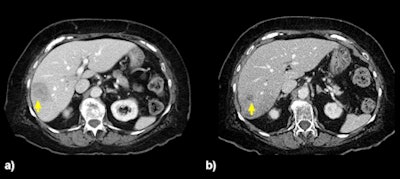

An 82-year-old woman with a 4.5 x 3.3-cm solitary tumor (a) in the right lobe. CT five months later (b) shows a reduction in size to 1.3 x 1.3 cm after two right lobar treatments at 93 Gy followed by 119 Gy. This patient had isolated liver metastases and remained free of extrahepatic disease 666 days after the first Y-90 treatment. Images courtesy of Dr. Robert Lewandowski.CT follow-up was available for 69 (94.5%) of 73 living participants. The scans showed that 29 individuals (42%) had a partial response with Y-90 radioembolization, while 40 (58%) experienced stable disease with no progression.